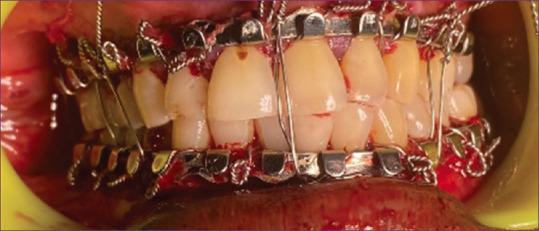

Evaluation of Bone Supported Ultra Lock Ezy Bar versus Erich Arch Bar for the Treatment of Mandibular Fractures.

Maxillofacial trauma treatment involves maxillomandibular fixation. Despite reduced need for post-operative MMF with plating devices, temporary intraoperative MMF is still necessary for proper tooth positioning. The aim of this research is to evaluate the cost-effectiveness, impact on patient gingival health, glove perforation, and time required for utilizing the Ultra Lock Ezy Bar compared to Erich's Arch Bar.

METHODS

Ten patients with mandibular fractures were randomly split into two groups for treatment: Group A (study) and Group B (control). Group A received treatment with an Ultra Lock Ezy Bar and screws, while Group B received treatment using an Erich's Arch Bar and wires. Follow-ups were done for suture removal, wound healing, and evaluations on gingival index, glove perforations, and treatment times.